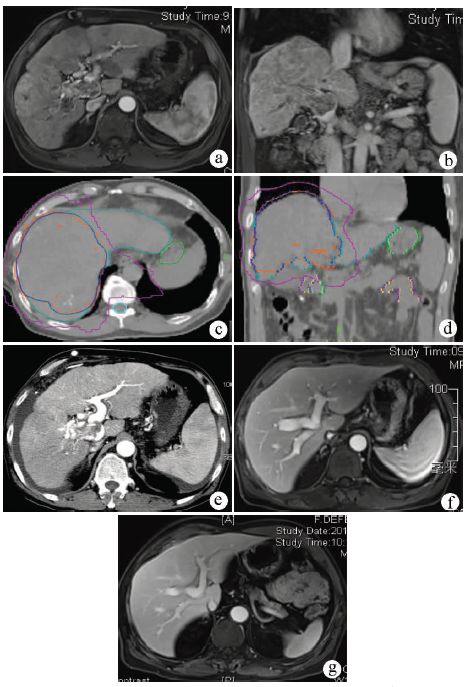

上海东方肝胆外科医院进行一项随机前瞻多中心的临床研究[4],比较肝细胞癌伴门静脉癌栓患者的术前新辅助放疗与不放疗的生存情况,放疗组82例,给予18 Gy/6次的新辅助外放疗;对照组82例,未行新辅助放疗。结果显示:新辅助放疗组的1、2年生存率分别为75.2%、27.4%,对照组分别为43.1%,9.4%,两组生存率有统计学差异(P<0.001)。新辅助放疗明显提高肝细胞癌患者的术后生存期。病例2是门静脉主干癌栓,经过新辅助放疗,癌栓从程氏Ⅲ型降为Ⅱ型,最后获得手术切除(图2)。

注:a,放疗前MRI检查,发现门静脉主干和右后支癌栓(箭头所示);b,放疗后3个月随访MRI,癌栓明显缩小,血供减少(箭头所示),患者获得切除机会。

图2 新辅助放疗后门静脉癌栓程氏Ⅲ型降为程氏Ⅱ型

对超出肝细胞癌移植标准的患者,接受外放疗可以缩小病灶,特别是作为窗口期,筛选出生物学行为好的肝癌患者,即使超出标准的肝细胞癌患者,也可能纳入肝移植标准,获得肝移植机会。而生物学行为差的肿瘤,在治疗过程中,向肝外转移,从而失去肝移植机会。笔者已经运用介入治疗结合外放疗,使得10余例肝癌伴门静脉癌栓患者获得肝移植机会,最长1例已存活11年。病例3是癌栓患者接受放疗后,肝内病灶缩小,长达5个月的窗口期观察,无远处转移,从而给予原位肝移植(图3)。类似研究在其他国家有所报道,但均是个例[6]。如,17例肝细胞癌伴门静脉癌栓患者,接受介入治疗结合放疗,随后接受肝移植,1、3年的生存率分别是87%和60%[7]。5例门静脉癌栓接受介入和介入后放疗,降期后再接受肝移植,其1、3年生存期为100%和80%,同一时期配对的10例(1∶2匹配)门静脉癌栓患者,单纯放疗,1、3年生存期仅50%和30%[8]。由于供体来源短缺,国内外这类研究尚处于起步阶段,需要进一步摸索。

注:a、b,MRI见门静脉主干、分支癌栓,肝内弥漫性病灶;c、d, CT扫描制定放疗计划,给予TOMO放疗50 Gy/25次,包括右叶及其门静脉主干;e,放疗后3周随访CT,门静脉癌栓明显缩小,但是腹水增多。于2011年9月28日接受肝移植。术后病理:肝内肿块14枚,最大位于肝右叶,5.5 cm×7.4 cm×3.5 cm,门静脉癌栓;f、g,移植术后5个月和6年随访MRI,无肝内复发,迄今存活8年。

图3 门静脉癌栓放疗后原位肝移植